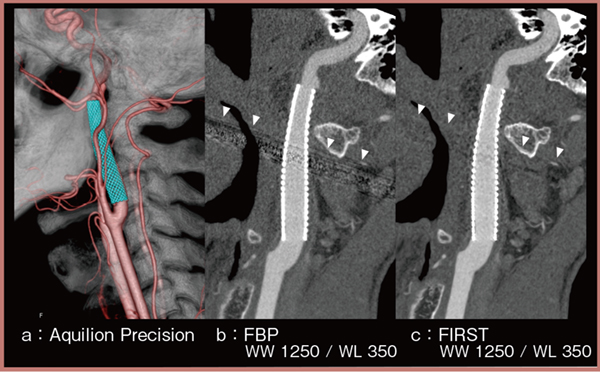

■頸動脈ステント術後評価における有用性1)

頸動脈ステント術後評価における高精細CTの有用性について,CTで評価しにくいコバルトベースのステントを対象に検討を行った。「Aquilion ONE / ViSION Edition」(従来CT)で撮影された画像でステント内腔を評価するには,ウインドウ条件をWW/WL=3000/1500のような極端な条件にする必要があるが,Aquilion Precision(図1)では極端な条件にすることなくステント内腔の評価が可能であった(b)。また,「Forward projected model-based Iterative Reconstruction SoluTion(FIRST)」(図1 c)を用いることで,アーチファクト(▼)を良好に低減できた。

経時的変化の評価においては,エコーで描出される内膜の肥厚をAquilion Precisionでも同様に評価することが可能であった。また,ステント内再狭窄の症例についても,Aquilion PrecisionではDSAと同様に再狭窄の状態を評価することができた。

このように,高精細CTは頸動脈ステント術後評価に有用であると考えられる。

図1 Aquilion Precisionによる頸動脈ステント術後評価

(参考文献1)より引用転載)